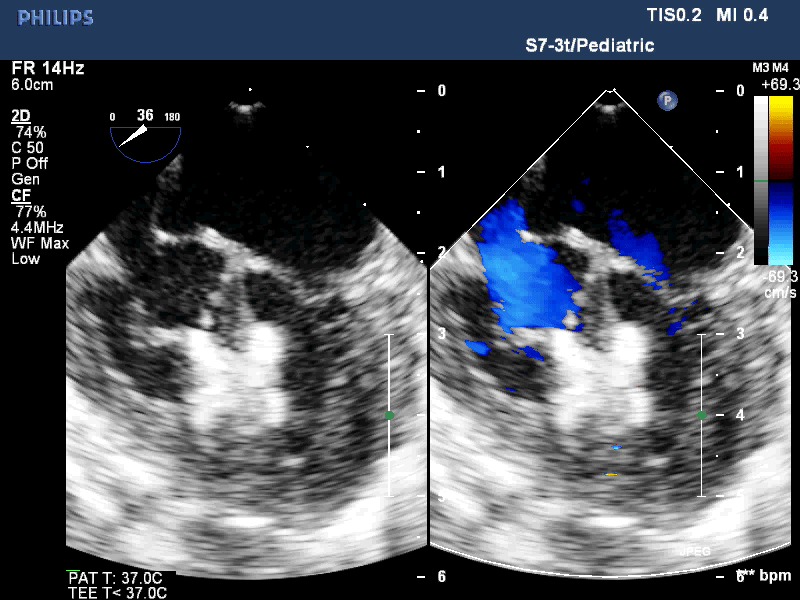

Операцию проводит бригада врачей под чреспищеводным эхокардиографическим (ЧП ЭХОКГ) контролем. После выполнения министернотомии используется пункция передней стенки правого желудочка.

В левый желудочек через ДМЖП вводится система доставки окклюдера. Затем производится последовательное открытия дистального и проксимального диска окклюдера. Таким образом, ДМЖП закрывается окклюдером, место прокола ПЖ ушивается, рана закрывается помощью косметической технологии.